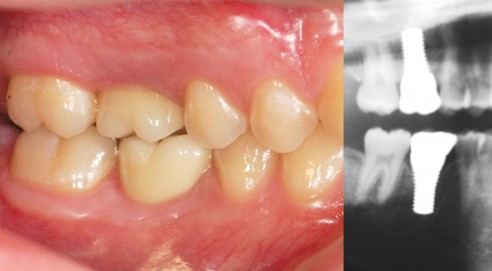

The inherent problem that frequently arises with titanium implants is an aesthetic one. Patients with thin, translucent gums or those who are prone to gum recession (as are many aging people) may end up with the gray gums or titanium showing around the margin of the crown. Since zirconia is non-metallic and white, it is much more natural looking than titanium. It’s a perfect base color that closely mimics what nature created in the first place.

A metal aura is visible around the gum line of the two upper front teeth with metal/ceramic crowns. In addition to aesthetic issues, the teeth were deemed endodontic failures. The surgical treatment plan included two tooth extractions and the immediate placement of CeraRoot implants. After healing, all-ceramic crowns were cemented onto the implants, and the final result is a beautiful, natural smile.